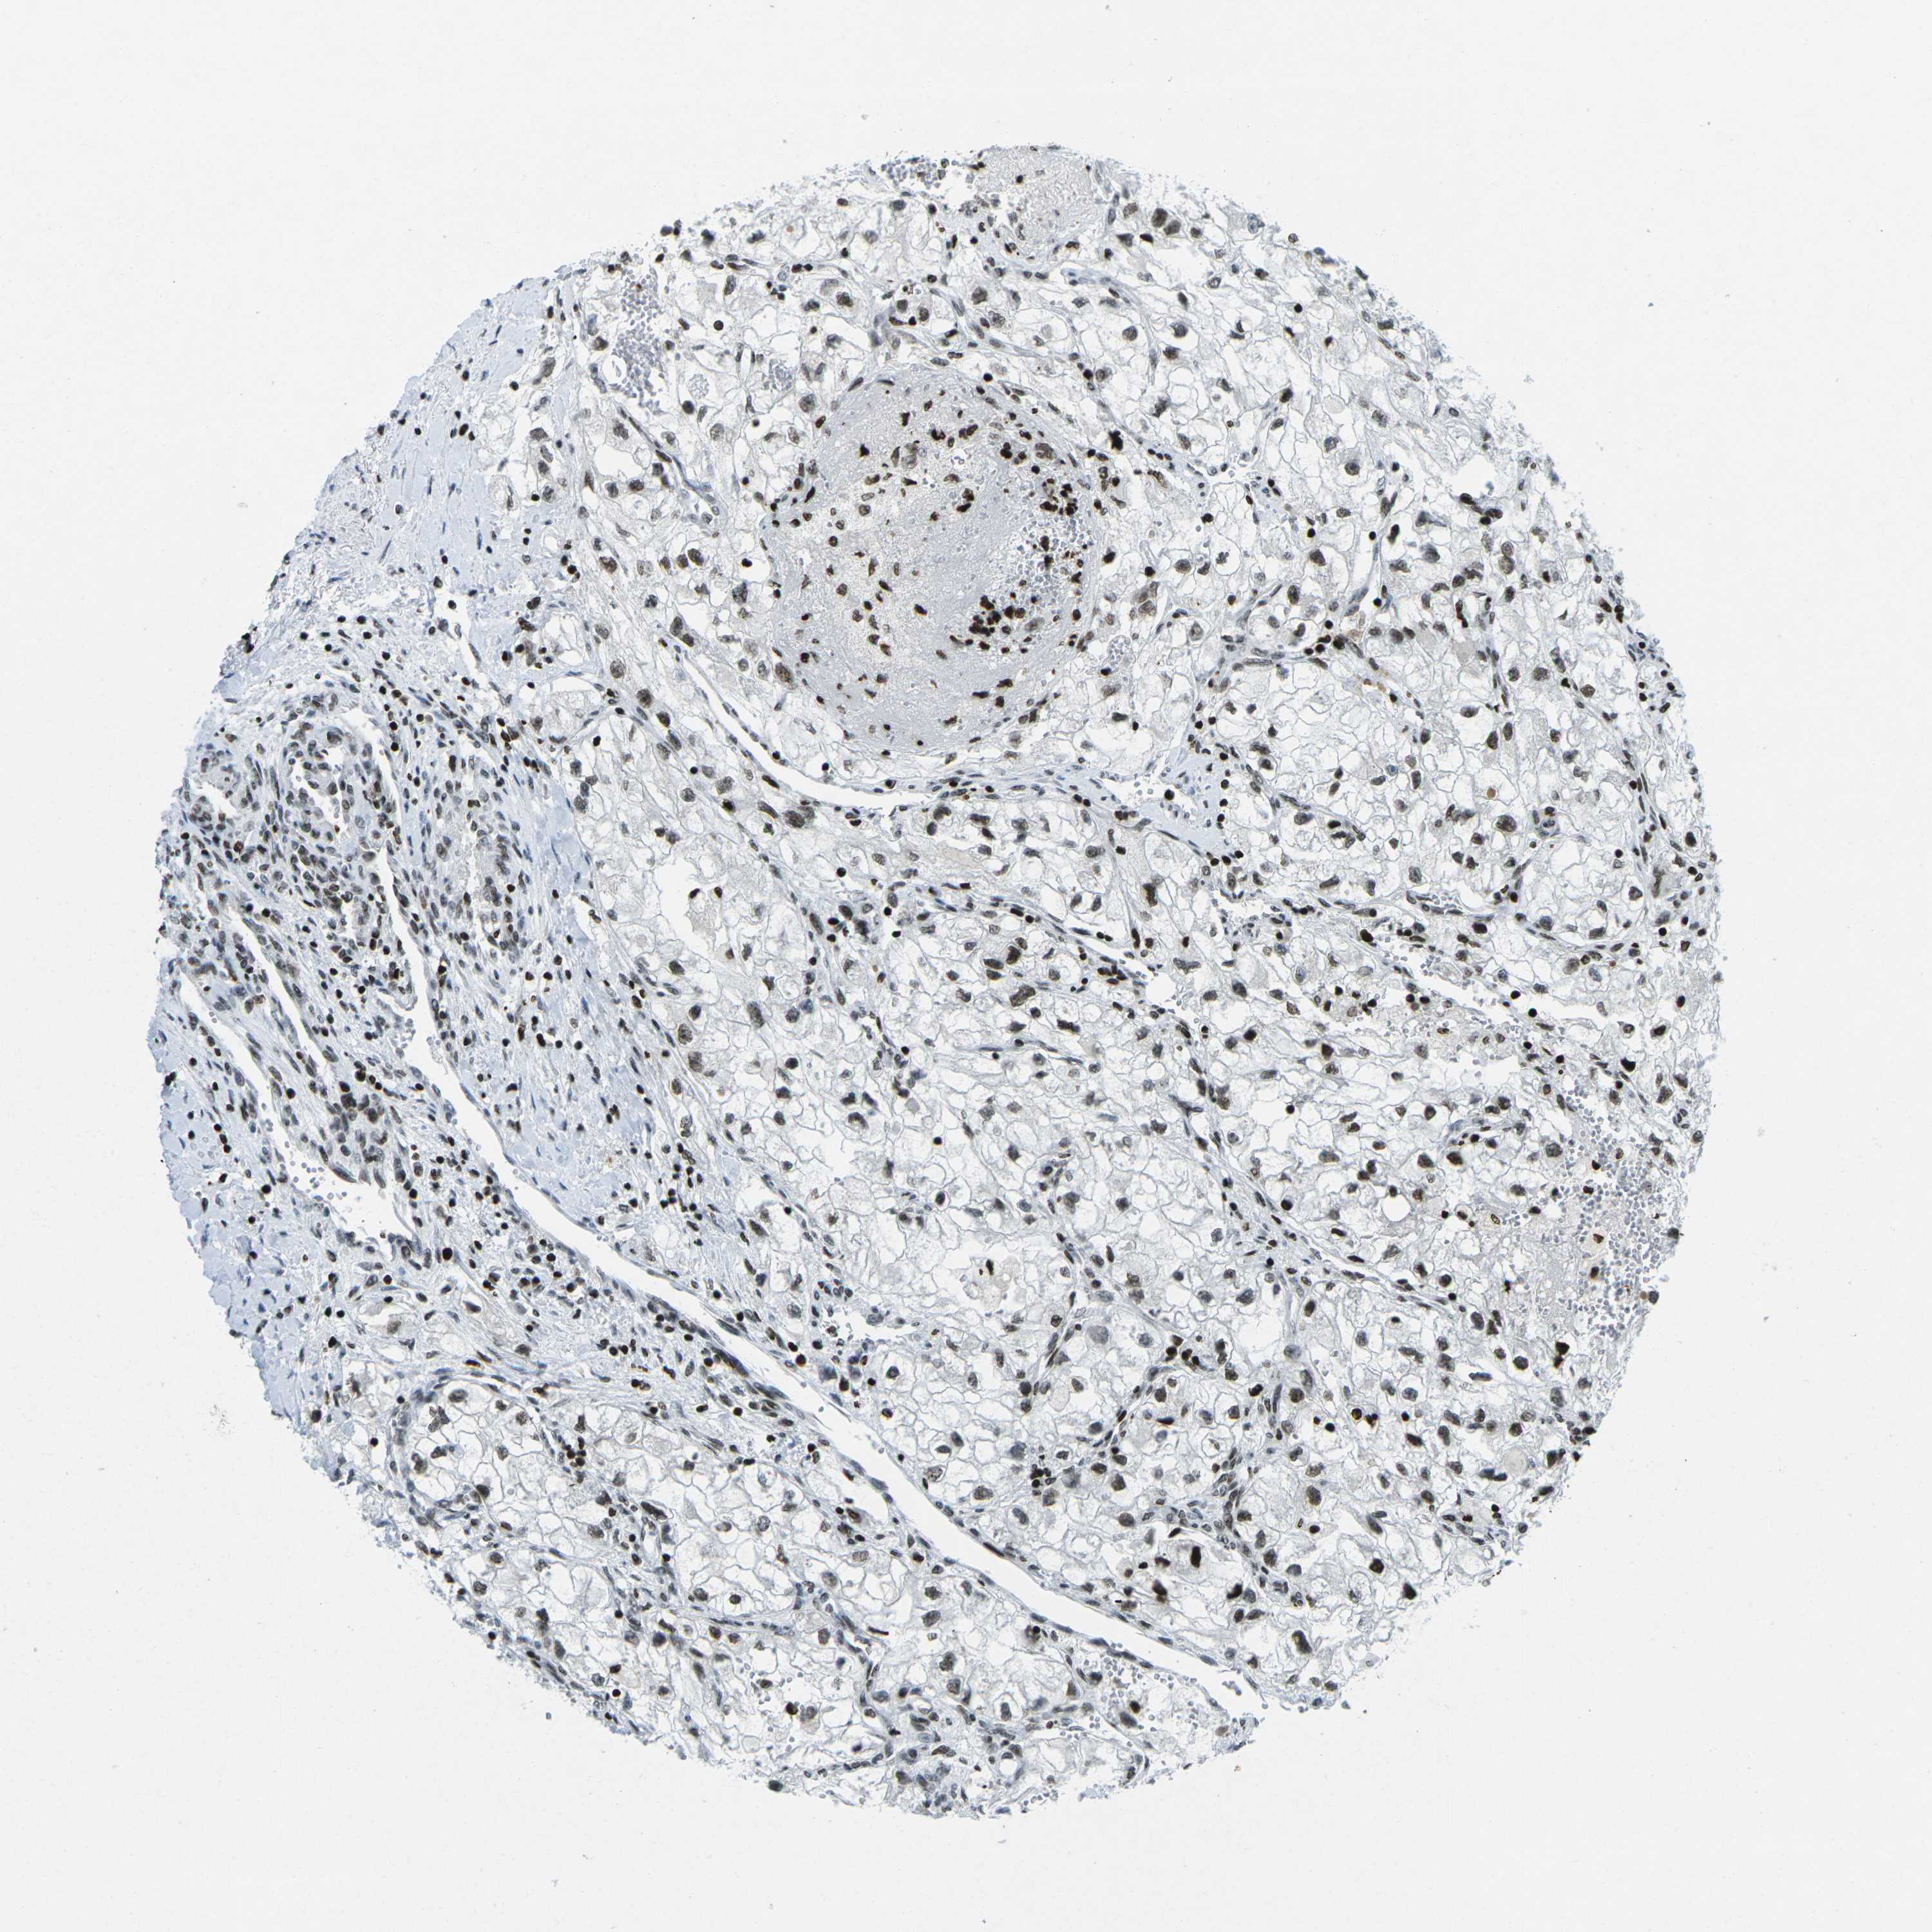

KIDNEY RENAL CLEAR CELL CARCINOMA (VALIDATION) - Interactive survival scatter ploti

The Survival Scatter plot shows the clinical status (i.e. dead or alive) for all individuals in the patient cohort, based on the same data that underlies the corresponding Kaplan-Meier plots. Patients that are alive at last time for follow-up are shown in blue and patients who have died during the study are shown in red.

The x-axis shows the expression levels (FPKM) of the investigated gene in the tumor tissue at the time of diagnosis. The y-axis shows the follow-up time after diagnosis (years). Both axes are complimented with kernel density curves demonstrating the data density over the axes. The top density plot shows the expression levels (FPKM) distribution among dead (red) and alive patients (blue). The right density plot shows the data density of the survived years of dead patients with high and low expression levels respectively, stratified using the cutoff indicated by the vertical dashed line through the Survival Scatter plot. This cutoff is automatically defined based on the FPKM cutoff that minimizes the p-score. The cutoff can be changed by dragging the vertical line or by entering a cutoff value in the square labeled "Current cut-off".

Under the Survival Scatter plot the p-score landscape (black curve; left axis) is shown together with dead median separation (red curve; right axis). Dead median separation is the difference in median mRNA expression between patients who have died with high and low expression, respectively. It is calculated as follows: median FPKM expression of dead patients with high expression - median FPKM expression of dead patients with low expression. This is intended to aid the user in visually exploring custom cutoffs and the associated p-scores and dead median separation.

Individual patient data is displayed and can be filtered by clicking on one or more of the category buttons on the top of the page. Categories describing expression level and patient information include: high, low, alive, dead, female, male and tumor stages. The scale of the x-axis can be toggled between linear and log-scale by clicking on the "x log" button. Mouse-over function shows TCGA ID, patient information and mRNA expression (FPKM) for each patient.

& Survival analysisi

Kaplan-Meier plots summarize results from analysis of correlation between mRNA expression level and patient survival. Patients were divided based on level of expression into one of the two groups "low" (under cut off) or "high" (over cut off). X-axis shows time for survival (years) and y-axis shows the probability of survival, where 1.0 corresponds to 100 percent.

EME1 is potential prognostic, high expression is unfavorable in Kidney Renal Clear Cell Carcinoma (validation)

Best expression cut offi

Based on the FPKM value of each gene, patients were classified into two groups and association between prognosis (survival) and gene expression (FPKM) was examined. The best expression cut-off refers the FPKM value that yields maximal difference with regard to survival between the two groups at the lowest log-rank P-value. Best expression cut-off was selected based on survival analysis .

When clicking on this number, the vertical dashed line indicating cut-off, the interactive survival plot, and the Kaplan-Meier curve will be adjusted to show results based on the best expression cut-off.

: 1.22